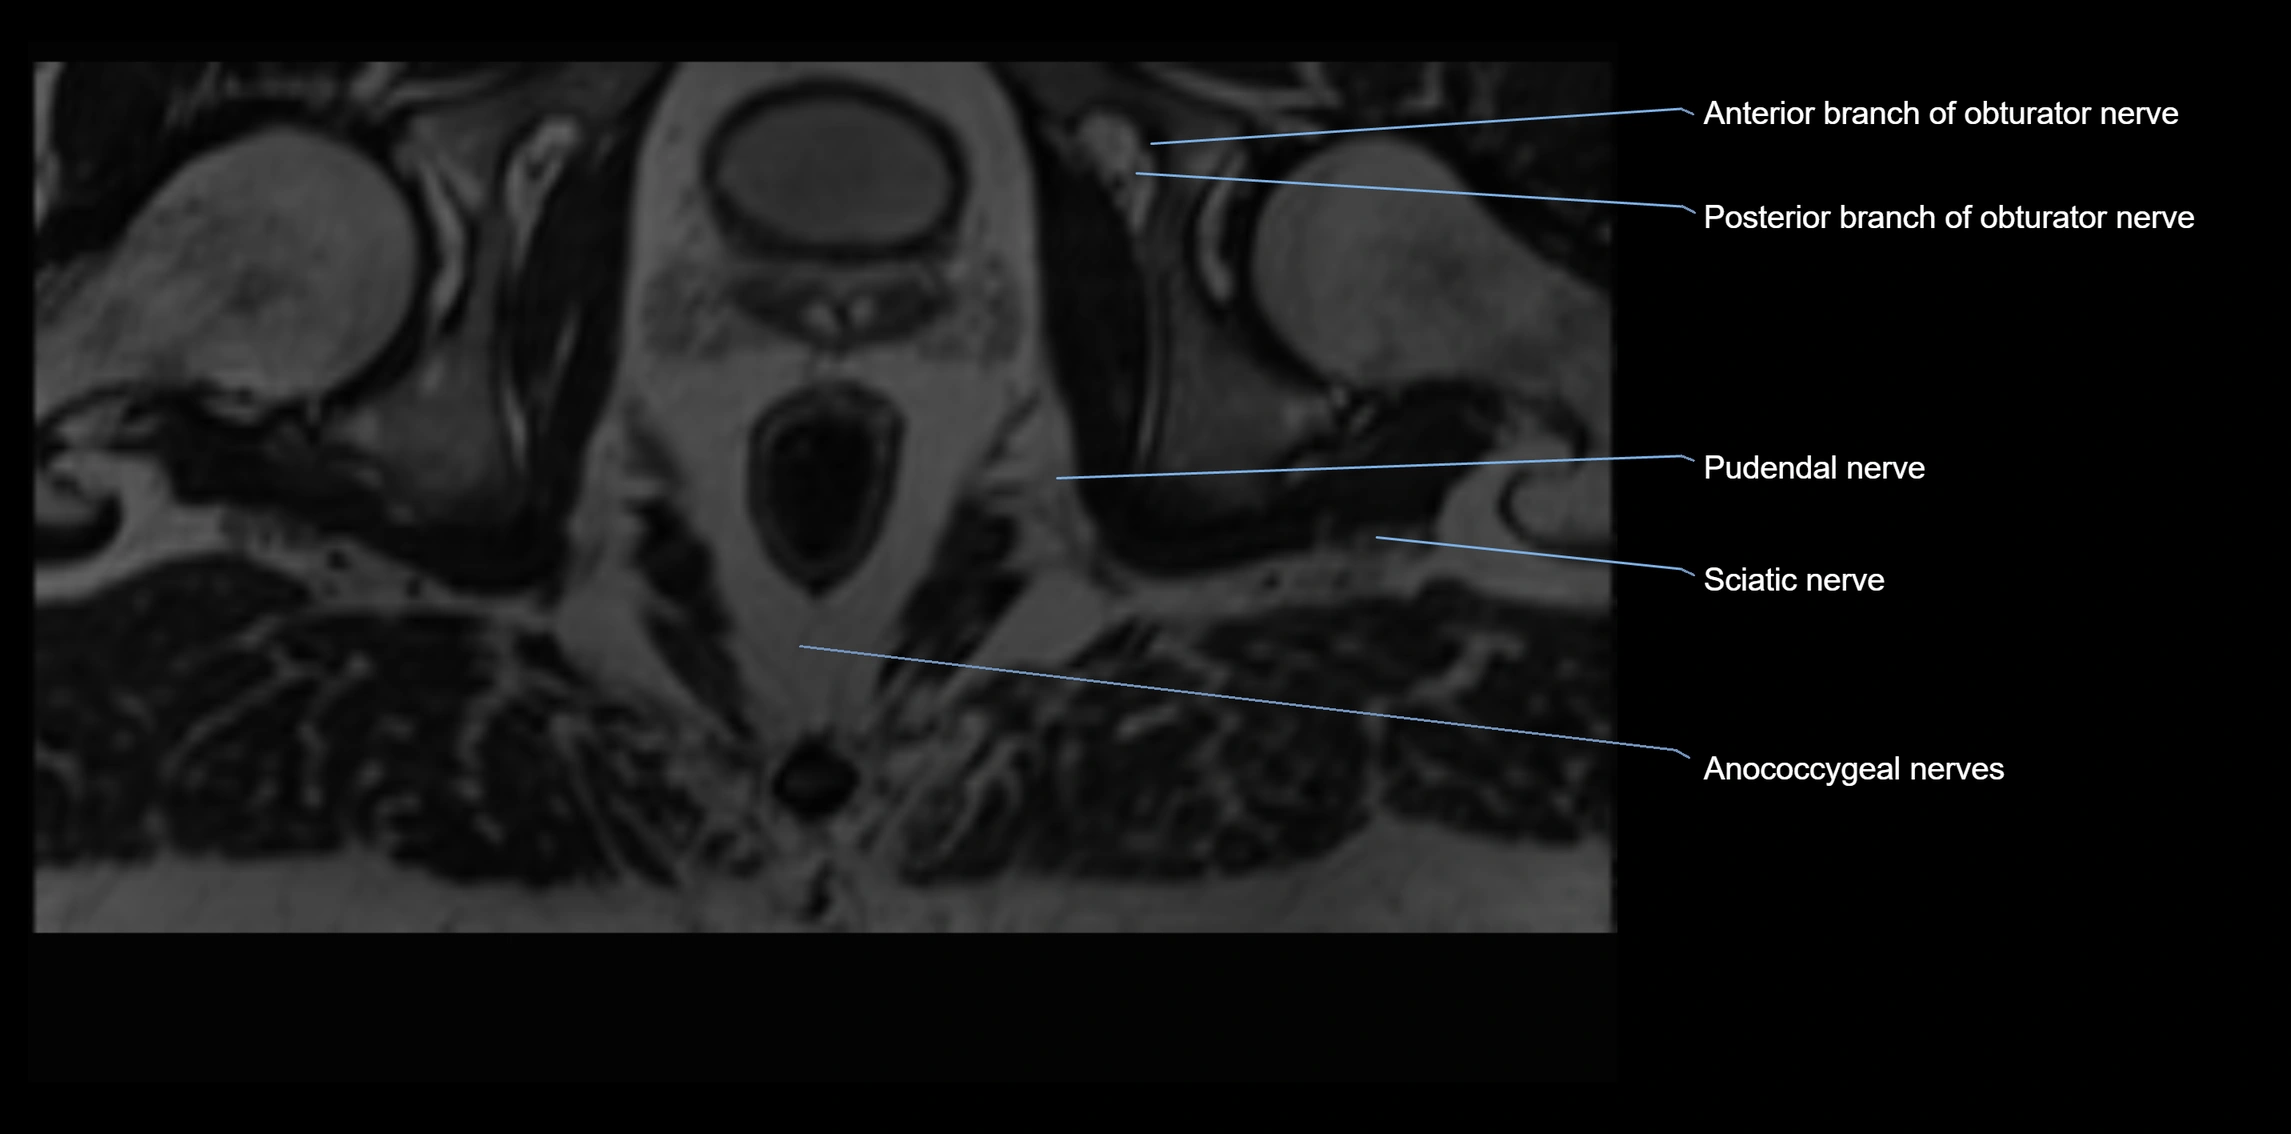

MRI image

image